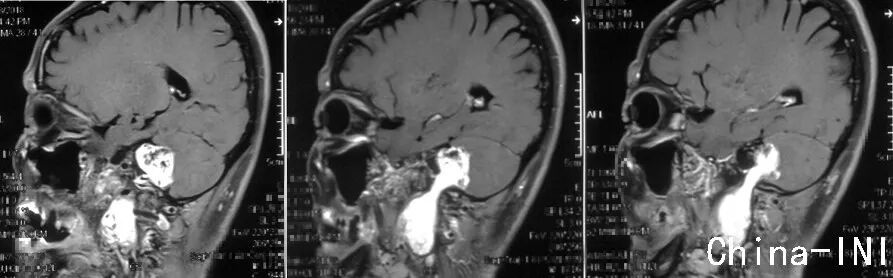

MRI轴位增强像示左侧颈静脉孔区神经鞘瘤,肿瘤呈哑铃型,同时侵及颅内、颈静脉孔及颈部,属于Samii颈静脉孔神经鞘瘤分型之D型,Fukushima分型之C型。

MRI冠状位增强像示肿瘤同时波及颅内、颈静脉孔及颈部,上端接近小脑幕水平,下端达第三颈椎水平。

MRI矢状位增强像示肿瘤呈哑铃型,从颅内经颈静脉孔,向颈部延伸到第三颈椎水平。

左侧颈静脉孔轻微扩大,边缘光滑,舌下神经管及颈动脉管未受累,这是神经鞘瘤的特征;如果是颈静脉球瘤,骨质会呈“虫蚀样”改变,破坏明显;脑膜瘤可伴有骨质增生。肿瘤外侧界为茎乳孔,为暴露颈静脉孔内肿瘤,术中需磨除枕骨颈静脉突。